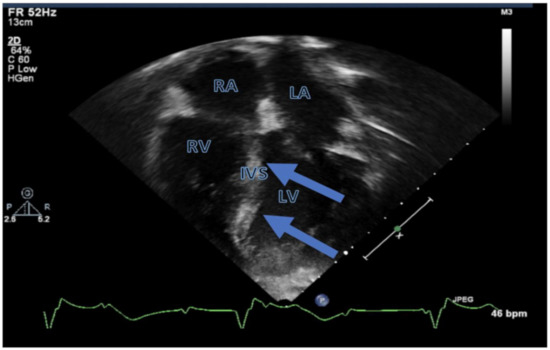

| Symptomatic cardiac relapse |

| 22 months | Refractory disease |

| Death due to severe LV systolic dysfunction and loss of AV conduction |